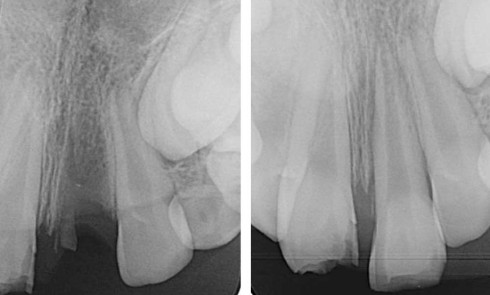

Article réservé à nos abonnés Extraction, implantation et temporisation immédiate : recycler la dent naturelle ? À propos d’un cas clinique

Les protocoles d’extraction-implantation immédiate, décrits pour la première fois en 1976 par Schulte et Heimke [1], se sont progressivement développés...